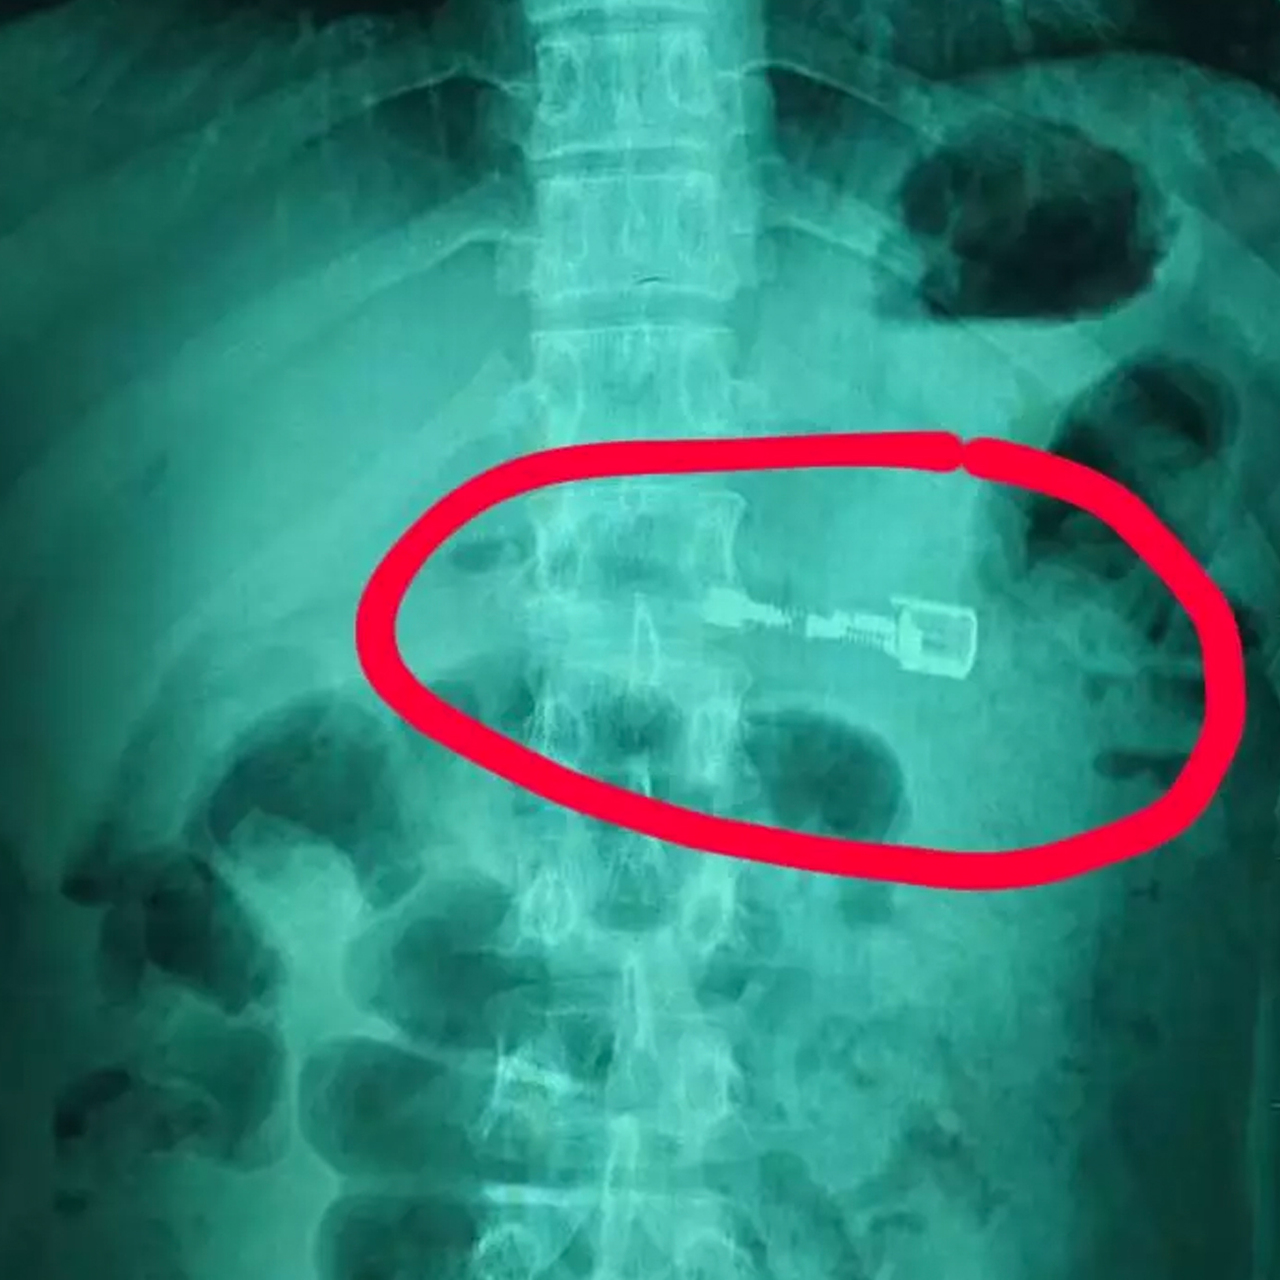

проглотил стекло

Что будет если случайно проглотил стекло 107 фотографий